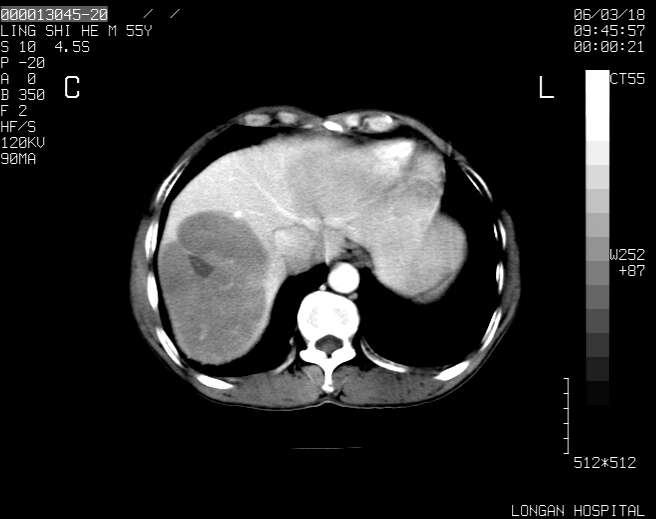

以下是引用guzhongliangddd在2006-3-21 22:13:00的发言:[br]病灶主要位于肝右叶的后份,内见异常血管,门脉主干及右支受侵{提示有癌栓形成},门腔间隙内见增大淋巴结。肝左叶内未见异常。

以下是引用zhuxinli在2006-3-22 1:23:00的发言:[br][br] 病灶主要位于肝右叶的后份,内见异常血管 .门脉右支截断,右叶前段早期强化(考虑动静脉漏),腹膜后肿大淋巴结,病灶逐渐强化,考虑为胆管细胞癌[br]